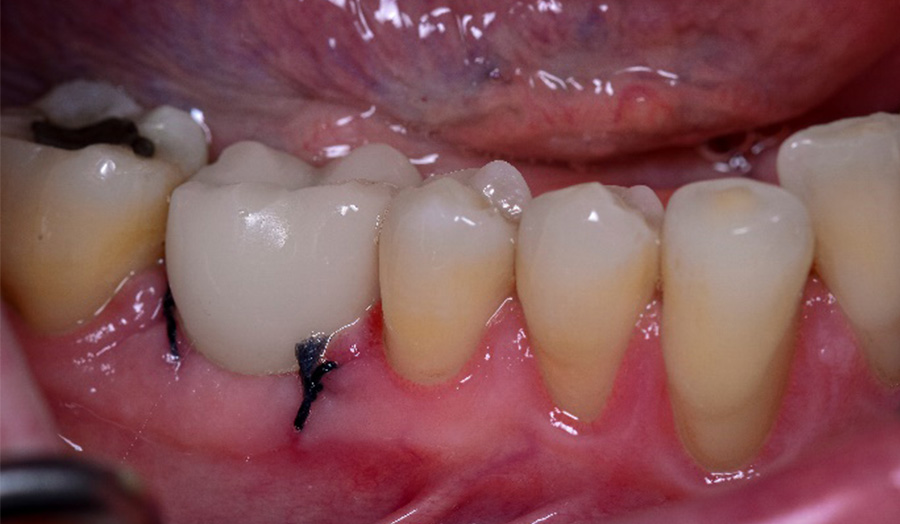

A 62-year-old male presented himself to my practice with a fractured non-restorable tooth #10. We planned a single implant with a surgical guide and a temporary bridge, both manufactured with Primeprint. The surgery was completed in 20 minutes, and it took us 10 minutes to bond the temporary bridge.

Before: Initial situation with a fractured non-restorable tooth #10